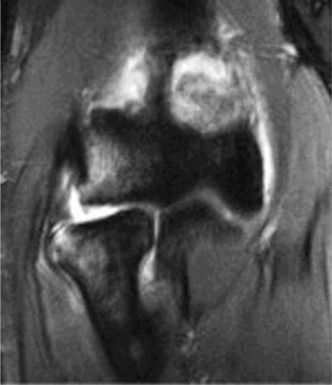

Examination reveals deformity about the elbow with no open lesions or skin tenting. He has a palpable radial and ulnar pulse and is neurologically intact. His images are shown (Figs. 2–85 to 2–88).

Figure 2–85

Figure 2–86

Figure 2–87

Figure 2–88

What is the diagnosis and direction of displacement?

Discussion

The correct answer is (B). This is the most common type of elbow dislocation, and often does not cause any osseous injury. Posterolateral and posteromedial dislocation account for approximately 90% of dislocations. Adequate pre- and postreduction films are necessary to evaluate for fracture, which would change the classification to a complex injury.